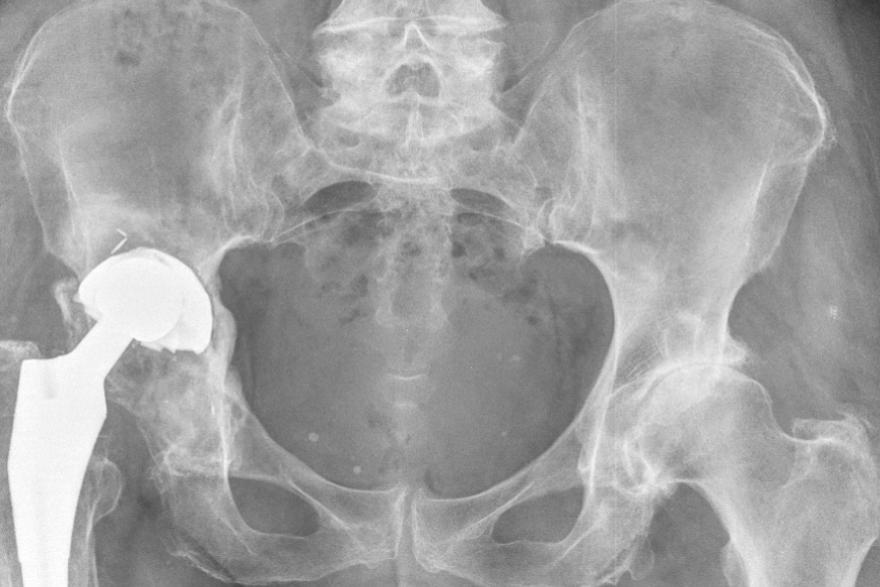

72-летней женщине врачи Центра Илизарова установили индивидуальный тазовый компонент с использованием аддитивных технологий. Пациентка попала к медикам с нестабильностью эндопротеза.

- В результате длительно нерешаемой проблемы, у пациента сформировался большой дефект тазовой кости в области вертлужной впадины, - отметили в пресс-службе Центра .

Из титана напечатали индивидуальный имплантат сложной формы для будущего эндопротеза, определили направление и подсчитали длину каждого винта, сделали технологические отверстия в тазовом компоненте.

- Из пластика был изготовлен прототип дефекта и направитель для винтов, чтобы хирурги могли четко спланировать дальнейшее хирургическое лечение, - уточнили в Центре Илизарова .